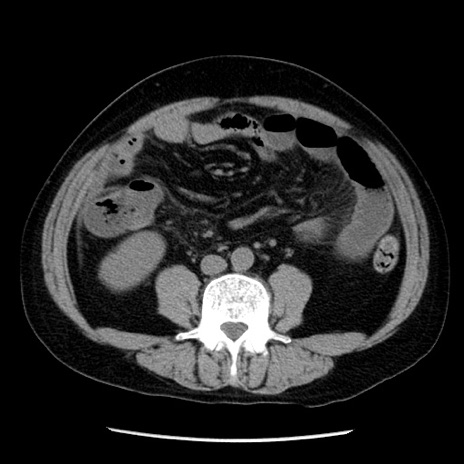

症例29(横断像)

【症例】40歳代男性

【現病歴】2日前から胃痛あり。徐々に周期的な激痛に変化した。本日になっても激痛があるため受診。

【身体所見】意識清明、BT 38-39℃台あり、腹部:膨満、やや硬、右下腹部に圧痛あり。

【データ】WBC 8500、CRP 23.26